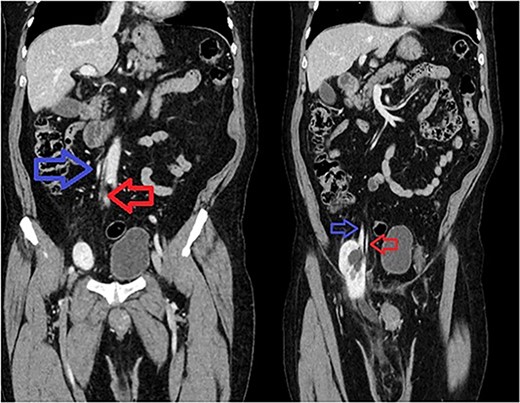

A 66-year-old Hispanic male presented to our emergency department with 1 week of right groin pain and swelling. He came to the hospital due to worsening pain. He denied any nausea, emesis or fever. He was passing gas and having bowel movements without difficulty. He denied any issues with voiding, hematuria or urinary urgency. His past medical history includes congenital deformity of his left upper extremity and past surgical history of open left inguinal hernia repair. His BMI is 32.5. His serum creatinine was 1.40 mg/dL. He had a normal white blood cell count at 9.8 × 103/UL and hemoglobin at 14.1G/DL. On examination, he had right inguinal tenderness to palpation with an obvious hernia extending to the scrotum. No skin changes were present. We were unable to reduce the hernia at bedside due to pain. A computed tomography (CT) of abdomen and pelvis with IV contrast showed herniation of the right kidney in the right inguinal hernia with the upper pole in the inguinal canal. The right renal artery and vein arose from the aorta and inferior vena cava, respectively, around the level of L1-L2 region (Fig. 1). The right ureter was incarcerated within the hernia and dilated up to 2 cm in diameter. The ureter transitions to normal caliber as it exits the hernia, concerning for obstructive uropathy (Fig. 2).

Incarcerated right kidney (white) in the inguinal hernia with distended ureter within the hernia sac (yellow).